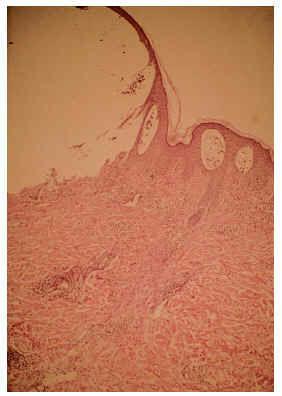

El estudio histopatológico de una lesión de contenido líquido reveló una ampolla subepidérmica, con un infiltrado perivascular en dermis superficial con predominio de eosinófilos, que también se hallaban en el interior de la ampolla (fig. 2). Con la inmunofluorescencia directa se encontraron depósitos de IgG y C3 a nivel de la membrana basal (fig. 3) y la indirecta demostró anticuerpos frente a la membrana basal a títulos de 1/80. La inmunofluorescencia directa del lado sano fue negativa.

Fig. 2.--Detalle de un lateral de la ampolla, con infiltrados perivasculares de eosinófilos y en el interior de la cavidad (HE, x100).